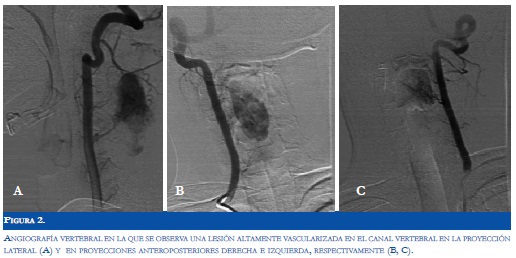

Paciente de sexo masculino de 16 años de edad, sin antecedentes patológicos relevantes, quién desarrolló dolor cervical asociado a espasmos musculares en dicha región, manejado hasta ese momento con medidas locales y analgésicos comunes. Dos meses después del inicio de estos síntomas, el paciente desarrolló monoparesia del miembro superior izquierdo y alteración sensitiva distal distal en el mismo miembro. Al ingreso a nuestra institución se encontró al paciente sin déficit en la esfera mental, ni alteraciones al examen físico general, pero con monoparesia de miembro superior izquierdo 2/5 y con hipoestesia ipsilateral en el dorso de la mano. Se realizó resonancia magnética (RM) de columna cervical en la cual se evidenció una lesión medular intraaxial cervical que comprometía desde la altura del cuerpo vertebral C2 hasta C5, de intensidad mixta y que captaba activamente el medio de contraste, sin evidencia de nido vascular (Figura 1). Con base en lo anterior, se consideró la posibilidad de una neoplasia intramedular altamente vascularizada. La arteriografía medular cervical permitió observar una lesión neoplásica con vascularización tipo capilar y con drenaje por venas dorsales prominentes y permitió descartar la posibilidad de una malformación arteriovenosa (Figura 2).

El método diagnóstico inicial para estas lesiones es la RM. Los principales hallazgos documentados en la RM consisten en imágenes isointensas en T1 e hiperintensas en T2 con intensa captación del gadolinio (14-16). Sin embargo en algunos casos descritos, se han reportado patrones imaginológicos opuestos.